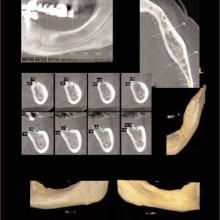

IMPACTIONS: Imaging can contribute greatly to localizing impacted teeth, identifying associated pathology, assist planning surgical access, and assist with designing the traction mechanics for moving the impacted tooth into the dental arch and occlusion (Figures 9, 10).

The anatomy sets some of the boundary conditions for tooth position. The identification and visualization of these boundary conditions can be performed by applying volumetric CT during initial workup. There are clinical instances when tooth movement is prevented or diminished because of anatomic boundaries, such as cortical margins, adjacent teeth, and dense bone. In addition, expansion of the dental arch form or tooth torque may be limited or confined by the labial and buccal cortical margins of the alveolar bone. These boundaries are difficult to visualize without the aid of cross sectional or three-dimensional imaging techniques (Figure 9).

With the traditional two-dimensional dental-imaging series some areas of anatomy are poorly visualized. These three-dimensional scans can give valuable information about other areas of the dentition such as the position of the upper incisor roots relative to the lingual cortical border of the palate to plan retraction, the amount of bone available in the posterior maxilla available for distalization, the amount of bone lateral to the maxillary buccal segments available for dental rather than skeletal expansion, airway information on the pharynx and nasal passages, upper root proximity to the maxillary sinus, the three-dimensional extent of an atrophied alveolar ridge, or the position of the lower incisor roots in bone. These scans also allow three-dimensional visualization of bony defects and supernumerary teeth in patients with cleft lip and/or palate. Additionally, axially corrected tomograms of the temporomandibular joints can be obtained from the same scan. The ability to visualize an axially corrected view of the temporomandibular joints with the teeth in occlusion on the same reconstructed section is one significant advantage of the volume scan. Therefore, there is substantial “value-added” imaging benefits to these scans for complicated orthodontic patients.